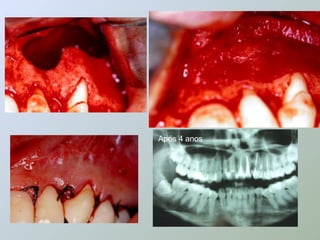

 Segundo Veiga & Guimarães,

essas barreiras, colocadas sobre

o defeito ósseo, impedem a

penetração de células epiteliais

e do tecido conjuntivo gengival,

favorecendo a proliferação de

osso alveolar no interior da lesão.

Após 4 anos